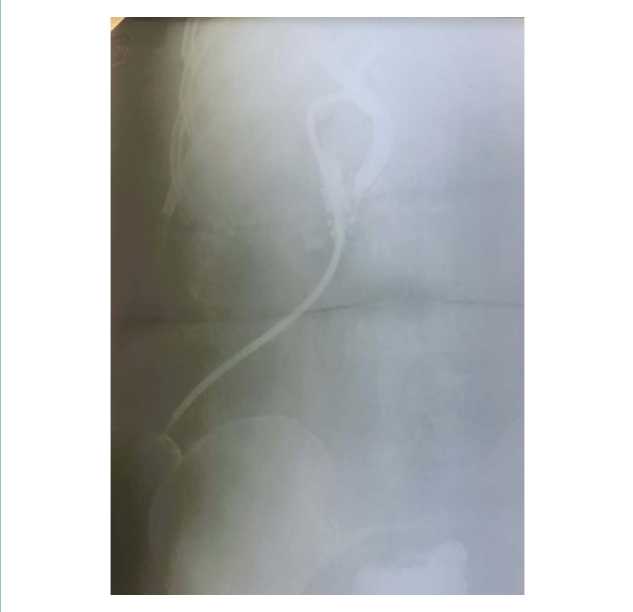

Из протокола операции. В брюшной полости: печень эластичная, кирпично-красного цвета. Желчный пузырь полностью не визуализируется, в области гартманова кармана образует плотный инфильтрат с подпаянной 12-перстной кишкой. При разделении инфильтрата обнаружен пузырно-дуоденальный свищ. Выделены, перевязаны и пересечены пузырный проток и пузырная артерия. Желчный пузырь удален. Свищ разобщен. Дефект 12-перстной кишки по передней стенке до 2 см в диаметре, ушит двухрядным швом нитью викрил 3,0 без сужения просвета. Холедох расширен до 10 мм, произведена холедохотомия, ревизия холедоха, извлечены конкременты диаметром 0,5 и 0,8 мм. Холедох промыт до чистых вод. Произведена ревизия холедоха в дистальном направлении зондом, зонд свободно проходит в 12-перстную кишку. Ревизия зондом общего, правого и левого печеночных протоков, проходимость не нарушена. Поступление чистой желчи из проксимального отдела холедоха. Интраоперационно проведена холангиография, пассаж контрастного вещества по билиарному тракту не нарушен (рис. 4).

![]()

Рисунок 4. Рентгеновский снимок интраоперационной холангиографии

Figure 4. Intraoperative cholangiography X-rayПроизведено ушивание холедоха наглухо узловыми швами. При дальнейшей ревизии определяются расширенные до 5 см в диаметре петли тонкой кишки. На расстоянии 1,5 от связки Трейца обнаружен камень, полностью обтурирующий просвет кишки. Дистальнее кишка спаявшаяся, вяло перистальтирует. Произведена энтеротомия с последующим извлечением камня. Энтеротомная рана ушита двухрядным швом нитью викрил 3,0. Послойно швы на рану. Послеоперационный период протекал без осложнений. Послеоперационная раны заживает первичным натяжением. Больная в удовлетворительном состоянии выписана на амбулаторное лечение под наблюдение хирурга поликлиники.